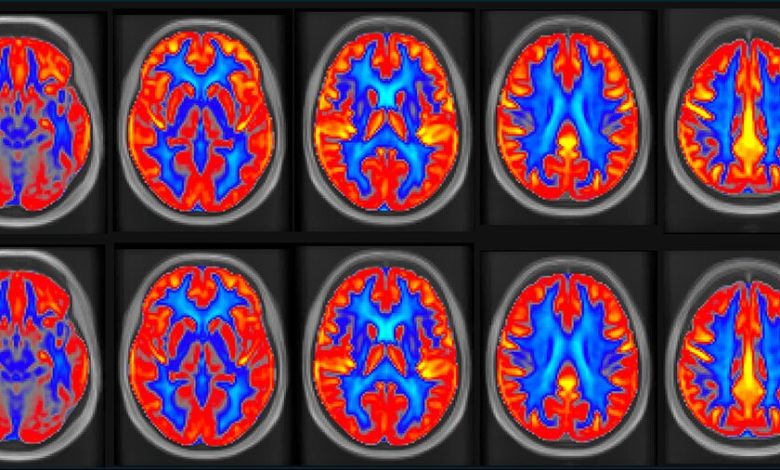

Mapas médios de fluxo sanguíneo cerebral (FSC) após (A) intervenção com amendoim e (B) períodos de controle em adultos (n = 31). FSC exibido em mL/100 g/min (escala mostrada pela barra colorida). Crédito: Dr. Peter Joris

O estudo NUTRIM com 31 idosos saudáveis com idades entre 60 e 75 anos observou que consumir 60 gramas (aproximadamente duas porções) de amendoim diariamente durante 16 semanas aumentou o fluxo sanguíneo cerebral global (FSC) em 3,6% e a memória verbal em 5,8%. Além das melhorias cerebrais, a pressão arterial sistólica e a pressão de pulso diminuíram em 5 mmHg e 4 mmHg, respectivamente.

A intervenção com amendoim também resultou no aumento do fluxo sanguíneo nos lobos frontal e temporal do cérebro, ambos importantes para a memória e outras funções cognitivas.

O estudo NUTRIM é único porque combinou uma intervenção dietética bem controlada e de longo prazo com técnicas avançadas de imagem cerebral, especificamente ressonância magnética (MRI) com marcação de rotação arterial, para investigar os efeitos do consumo diário de amendoim na saúde do cérebro. O desempenho cognitivo foi avaliado por meio da Bateria Automatizada de Testes Neuropsicológicos Cambridge (CANTAB).